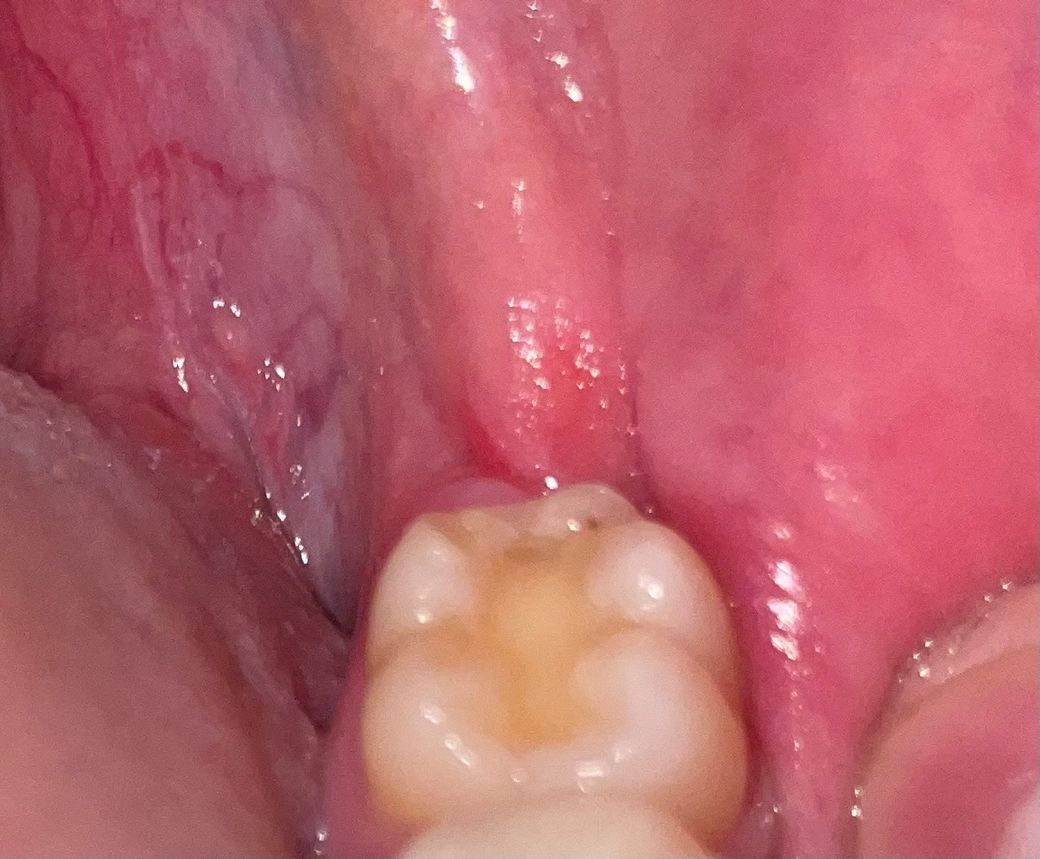

레진 치료한 자리에 검은 점이 보입니다.

오늘 스케일링 후 집에 와서 치아를 보니 1~2 년전 레진으로 치료했던 자리에 검은 점이 보입니다

의사분이 스케일링 후 별말씀은 안하셨는데 충치일까요?

사진상 레진 부위의 단순 착색이거나 변색일 가능성이 있어보입니다 시린증상이 있는지 보세요

사진에 보이는건 아마도 착색이 발생한거 같습니다. 큰 문제가 잇는건 아니니 너무 걱정하지마세요.

치과재료로 충전을 하고 나서 해당부위에 착색등이 생길수 있습니다. 크게 문제가 되는것은 아니지만 신경이 쓰인다면 착색이 된 부위만 제거하고 새로 충전할수 있습니다.